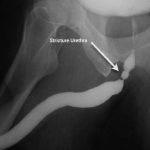

Değerlendirme sürecinde genellikle:

-

Üroflowmetri

Sistoskopi

Gerekirse retrograd üretrografi

gibi yöntemler kullanılarak darlığın yeri ve uzunluğu belirlenir. Bu bilgiler doğrultusunda kapalı yöntem mi yoksa açık cerrahi mi uygun olacağına karar verilir.